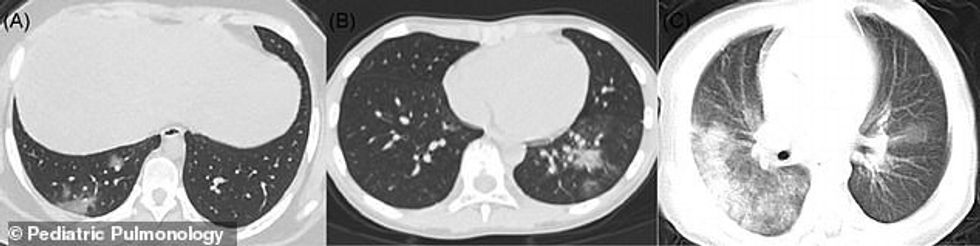

Dr Foust dhe kolegët morën pesë studime dhe vunë re ndryshimet më të dukshme në mushkëritë e fëmijëve, duke publikuar gjetjet e tyre në “American Journal of Roentgenology”.

Një studim në qytetin kinez Wuhan shikoi 20 pacientë të spitalit pediatrik me COVID-19 midis moshave të një dite dhe 14 vjeç. Trembëdhjetë ishin meshkuj.

Të gjithë pacientët kishin lezione – një pjesë e indeve që është dëmtuar ose është ndryshuar në mënyrë anormale – në muret e mushkërive.

Gjysma kishte lezione bilaterale në mushkëri, domethënë për të dy palët, ndërsa 30 përqind kishin lezione në vetëm një mushkëri.

Gjashtë në dhjetë pacientë kishin një GGO, e cila është një re e mjegullt mbi mushkëri që tregon një larmi problemesh.

Mund të nënkuptojë që mushkëritë janë të mbushura pjesërisht me lëndë jo të zakonshme, ka trashje të indeve të mushkërive ose kolaps të pjesshëm të valvuleve - qeskat e vogla ajrore të mushkërive.

Gjysma kishte konsolidim, që është hapësira ajrore në mushkëritë e tyre të mbushura me një substancë, zakonisht qelb, gjak ose ujë.